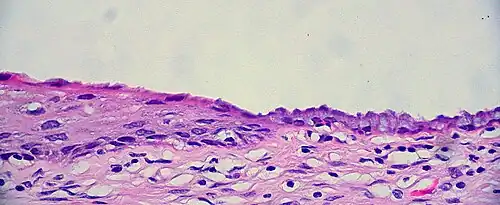

Transformation zone mucosa, when the squamocolumnar junction has a gradual transition. It consists of a mix of stratified squamous epithelium and mucinous glands. H&E stain.

The endocervical mucosa is about 3 mm (0.12 in) thick and lined with a single layer of columnar mucous cells. It contains numerous tubular mucous glands, which empty viscous alkaline mucus into the lumen.[4] In contrast, the ectocervix is covered with nonkeratinized stratified squamous epithelium,[4] which resembles the squamous epithelium lining the vagina.[17]: 41  The junction between these two types of epithelia is called the squamocolumnar junction.[17]: 408–11  Underlying both types of epithelium is a tough layer of collagen.[18] The mucosa of the endocervix is not shed during menstruation. The cervix has more fibrous tissue, including collagen and elastin, than the rest of the uterus.[4]

In prepubertal girls, the functional squamocolumnar junction is just within the cervical canal.[17]: 411  Upon entering puberty, due to hormonal influence, and during pregnancy, the columnar epithelium extends outward over the ectocervix as the cervix everts.[15]: 106  Hence, this also causes the squamocolumnar junction to move outwards onto the vaginal portion of the cervix, where it is exposed to the acidic vaginal environment.[15]: 106 [17]: 411  The exposed columnar epithelium can undergo physiological metaplasia and change to tougher metaplastic squamous epithelium in days or weeks,[17]: 25  which is very similar to the original squamous epithelium when mature.[17]: 411  The new squamocolumnar junction is therefore internal to the original squamocolumnar junction, and the zone of unstable epithelium between the two junctions is called the transformation zone of the cervix.[17]: 411  Histologically, the transformation zone is generally defined as surface squamous epithelium with surface columnar epithelium or stromal glands/crypts, or both.[20]